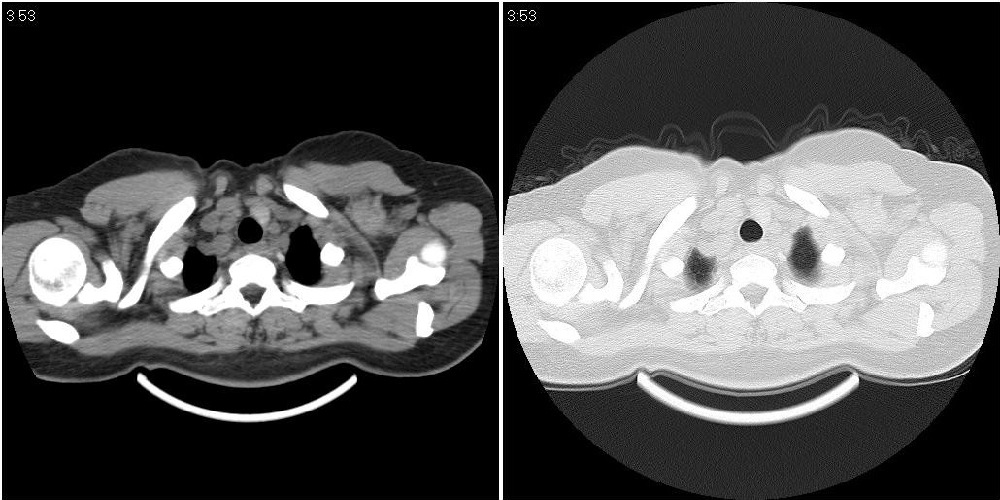

标题: CT24795:女性,47岁,右下腿静脉静脉曲张手术前体检,发现 [打印本页]

标题: CT24795:女性,47岁,右下腿静脉静脉曲张手术前体检,发现

囊性无明显占位效应:1淋巴管囊肿2畸胎瘤(其上部见小钙化)3前肠囊肿

右上纵隔囊性占位性病变;考虑淋巴管囊肿,不排除支气管囊肿。

支气管囊肿、囊性畸胎瘤、肠源性囊肿均有可能。

右上纵隔囊性占位性病变;考虑淋巴管囊肿,不排除支气管囊肿。 建议增强。

考虑淋巴管囊肿,不排除前肠囊肿。